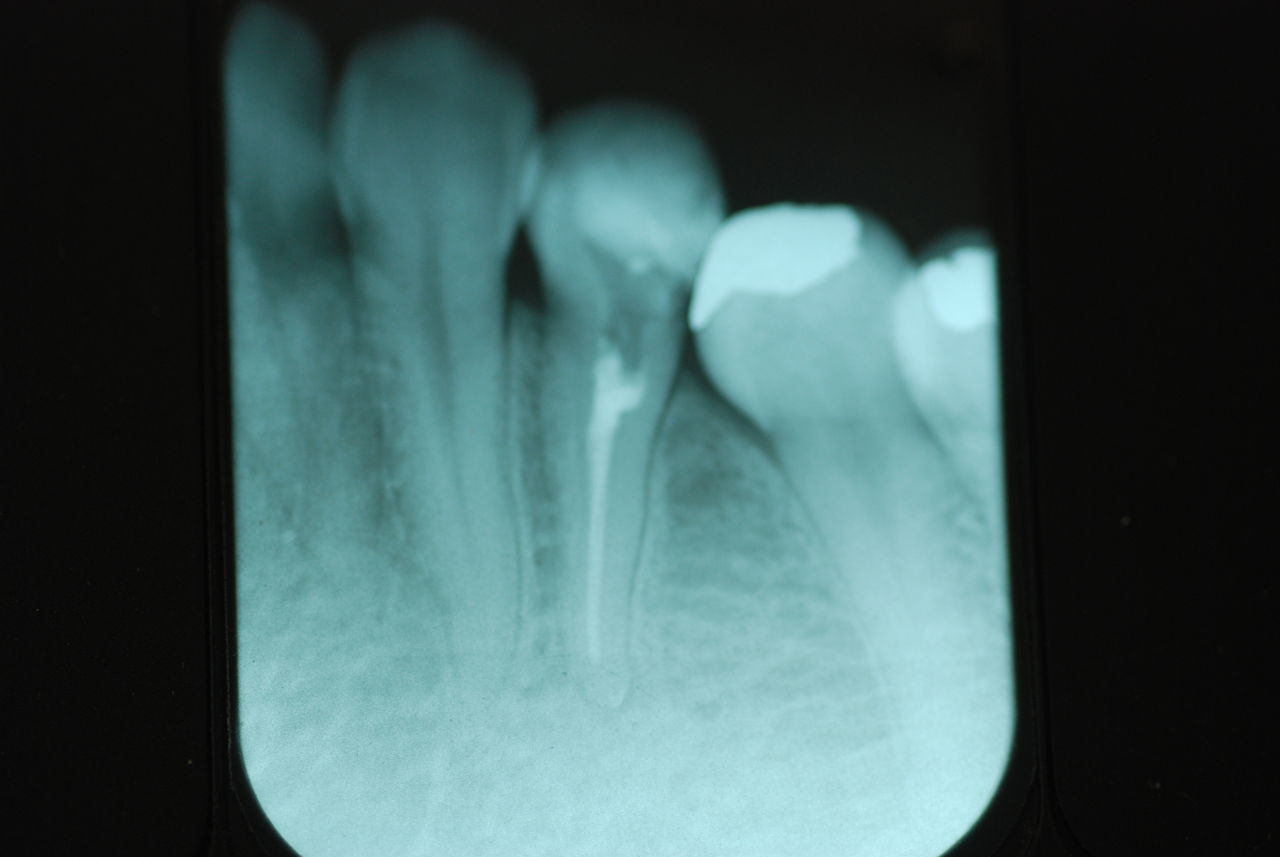

左下の歯は歯の中の治療も?ですごい歯周病を患い歯茎の穴(ポケットと呼ばれるところ)から膿が出ているのです。ばい菌と毒素で骨が溶けて深い穴ができてそこにまたバイキンと毒素がたまるという悪循環ができているのですね。